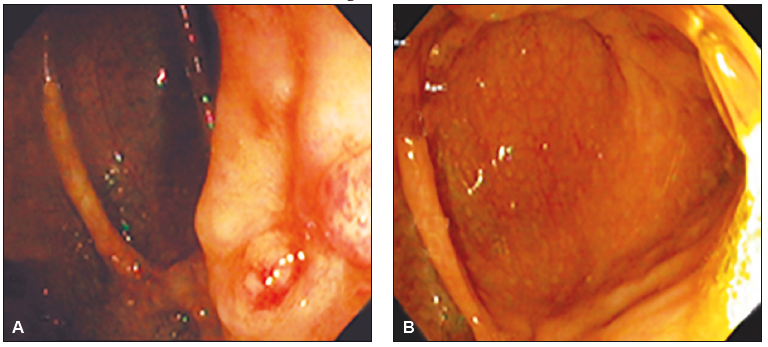

Posteriormente se revaloró con VEDA, en la que presentó mucosa normal y VCC, donde se observaron úlceras aftoides en el colon descendente (Figura 4) con los últimos 3 cm de íleon normales. Para completar el estudio del intestino medio se utilizó una cápsula endoscópica, mediante la cual se observaron úlceras aftoides y erosiones cubiertas por fibrina a nivel del yeyuno; en íleon medio-distal se constató la presencia de úlceras de diferente configuración y tamaño (menores a 2 cm), rodeadas de un halo eritematoso; en los 5 cm previos a la ileostomía la mucosa presentaba edema, eritema y hemorragias subepiteliales; el índice de Lewis fue moderado-severo (Figura 5).

Figura 4. Úlcera aftoide en el colon descendente

Figura 5. A. Ulceración en yeyuno. B. Úlcera lineal en yeyuno.

C. Úlcera cubierta con fibrina en íleon. D. Úlceras longitudinales y

circulares cubiertas con fibrina en íleon